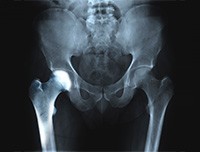

The hip joint is a ball-and-socket joint. A part of the pelvis bone known as the acetabulum forms the socket and the upper end of the femur, known as the femoral head, forms the ball. In patients with transient osteoporosis of the hip, the femoral head loses its density and strength and becomes more prone to breaking.

You will also be recommended to undergo imaging studies such as X-rays, CT scans, MRIs, or nuclear scans to further document transient osteoporosis of your hip.